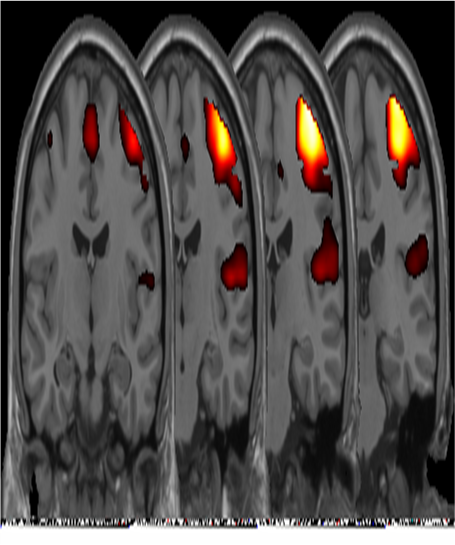

Activation of visual cortex Oxygenated and deoxygenated hemoglobin have different magnetic susceptibility. Brain tissue has a susceptibility closer to that of oxygenated hemoglobin. Therefore, with more deoxygenated hemoglobin in the blood, there is less disturbance in the magnetic fields and the spinning water molecules exposed to the magnetic fields see less difference in spin velocity between positions. As a result the net spin vector of the molecules stays larger and is measured as a larger MRI signal. Thus, blood with a greater fraction of oxygenated hemoglobin sees a larger signal. This corresponds with a greater fraction of oxygenated hemoglobin in active neurons.

Activation after memory task In the way described above, the neural activity in a location can be measured. fMRI is very good at localizing the area compared to other techniques of brain imaging such as PET, SPECT or EEG, but it is not as good as EEG at identifying the timing of neural activity. fMRI relies on the idea that specific areas of the brain are called in as necessary to perform a cognitive task. It also relies on people consistently using those specific areas.

Activation of motor cortex - left finger tapping The change in MRI signal with oxygenated hemoglobin fraction is very small and is complicated by a delayed response to the neural activity called the hemodynamic response. These things make it difficult to detect the pattern even in areas that are active. We do as much as we can, but in the end, the identification of active areas is a statistical decision and there is nothing certain.